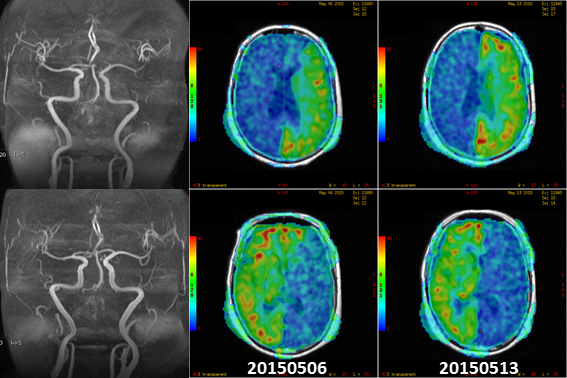

上图:69岁女性,间断头晕半年,加重两周,左侧颈总末端狭窄,12号进行颈总内膜剥脱手术。在tASL中可以观察到左右颈内动脉在手术前后灌注区域的改变。对于慢性一侧颈内动脉狭窄的病人,在建立侧枝循环的过程中,脑血管灌注会再分配,同时大部分患侧都是灌注减低。当狭窄解除后,血流灌注再次进行再分配,大部分患者都是灌注增高。这种灌注的快速变化,会导致脑过度灌注综合症。所以我们在术后进行脑组织灌注再分配显示及其定量分析就显得尤为重要。(病例取自北京协和医院) 在对脑血管类疾病供血的精细研究中,具有血管选择性的动脉自旋标记技术(Territorial ASL, tASL)因建立起了供血源与灌注区域的直接联系,往往可以发挥更大的价值。结合超选择与血管编码技术(super-selective ASL, ssASL[17];vessel-encoding ASL, veASL[18]),tASL可实现选择性地观察特定血管的供血灌注情况。这对于代偿支的灌注评估具有其他技术无可比拟的优势。 参考文献 [1] J. Detre, et al. Perfusion Imaging. MRM 1992 [2] D. Alsop, et al. Recommended Implementation of Arterial Spin Labeled Perfusion MRI for Clinical Applications: A Consensus of the ISMRM Perfusion Study Group and the European Consortium for ASL in Dementia. MRM 2014 [3] J. Wang, et al. Comparison of quantitative perfusion imaging using ASL at 1.5T and 4T. MRM 2002 [4] S. Kim. Quantitative of relative cerebral blood flow change by FAIR technique: application to functional mapping. MRM 1995 [5] E. Wang, et al. Implementation of quantitative perfusion imaging techniques for functional brain mapping using pASL. NMR Biomed 1997 [6] X. Golay, et al. PULSAR: a robust regional perfusion technique for high field imaging. MRM 2005 [7] G. Jahng, et al. Improved perfusion-weighted MRI by a novel DIPLOMA. MRM 2003 [8] R. Buxton. Introduction to Functional MRI: Principles and Techniques 2nd. 2009 [9] R. Irie, et al. Assessing Blood Flow in an Intracranial Stent: A feasibility study of MRA using a silent scan after stent-assisted coil embolization for anterior circulation aneurysms. AJNR 2015 [10] J. Wang, et al. The value of ASL perfusion imaging in acute ischemia stroke: Comparison with DSC MRI. Stroke 2012 [11] J. Boxerman, et al. Relative Cerebral Blood Volume Maps Corrected for Contrast Agent Extravasation Significantly Correlate with Glioma Tumor Grade, whereas Uncorrected Maps Do Not. [12] R. McDonald, et al. Intracranial Gadolinium Deposition after Contrast-enhanced MRI. Radiology 2015 [13] FDA: http://www.fda.gov/Drugs/DrugSafety/ucm455386 [14] Y. Li, et al. Cardiac-triggered pcASL: A cost-effective scheme to enhance the SNR of ASL. ISMRM 2015 [15] R. label. The many advantages of arterial spin labeling with long label duration. ISMRM 2015 [16] W. Dai, et al. Reduced Resolution Transit Delay Pre-scan for Quantitative Continuous Arterial Spin Labeling Perfusion Imaging. MRM 2012 [17] E. Wang. Vessel Encoded Arterial Spin-Labeling Using Pseudo-continuous Tagging. MRM 2007 [18] M. Helle, et al. Super-selective Pseudo-continuous Arterial Spin Labeling. MRM 2010